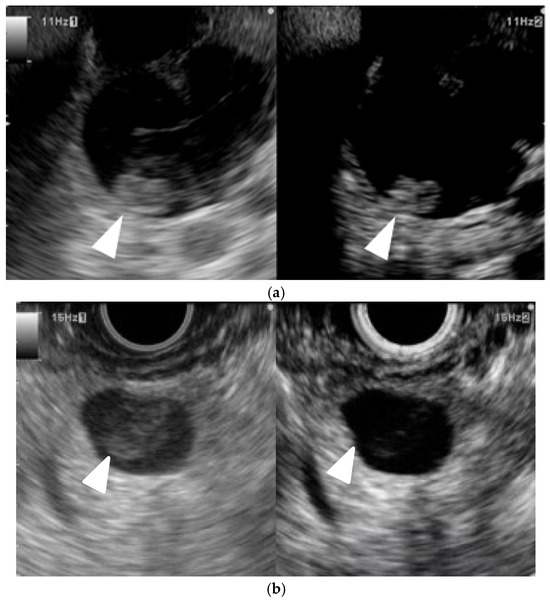

The incidence and mortality rate of pancreatobiliary cancer, which has a poor prognosis, are rising rapidly. Endoscopic ultrasonography (EUS) and abdominal ultrasonography play an important role in the diagnosis and treatment of this cancer, and abdominal ultrasonography is useful for the screening. EUS provides superior spatial resolution compared with other imaging modalities such as transabdominal ultrasound, computed tomography (CT), and magnetic resonance imaging (MRI), and it is considered among the most reliable and efficient diagnostic modalities for pancreatic lesions. Therefore, it is useful for the detection of small pancreatic lesions. Endoscopic ultrasound-guided fine-needle aspiration (EUS-FNA) has a high accuracy rate and low complication rate; thus, it is the final tool dictating the therapeutic strategy. EUS-FNA-related technique (interventional EUS) has been extensively applied to the treatment of pancreatobiliary diseases. This Special Issue aims to provide a comprehensive overview of recent advances in terms of both the diagnosis and treatment of pancreatobiliary cancer.